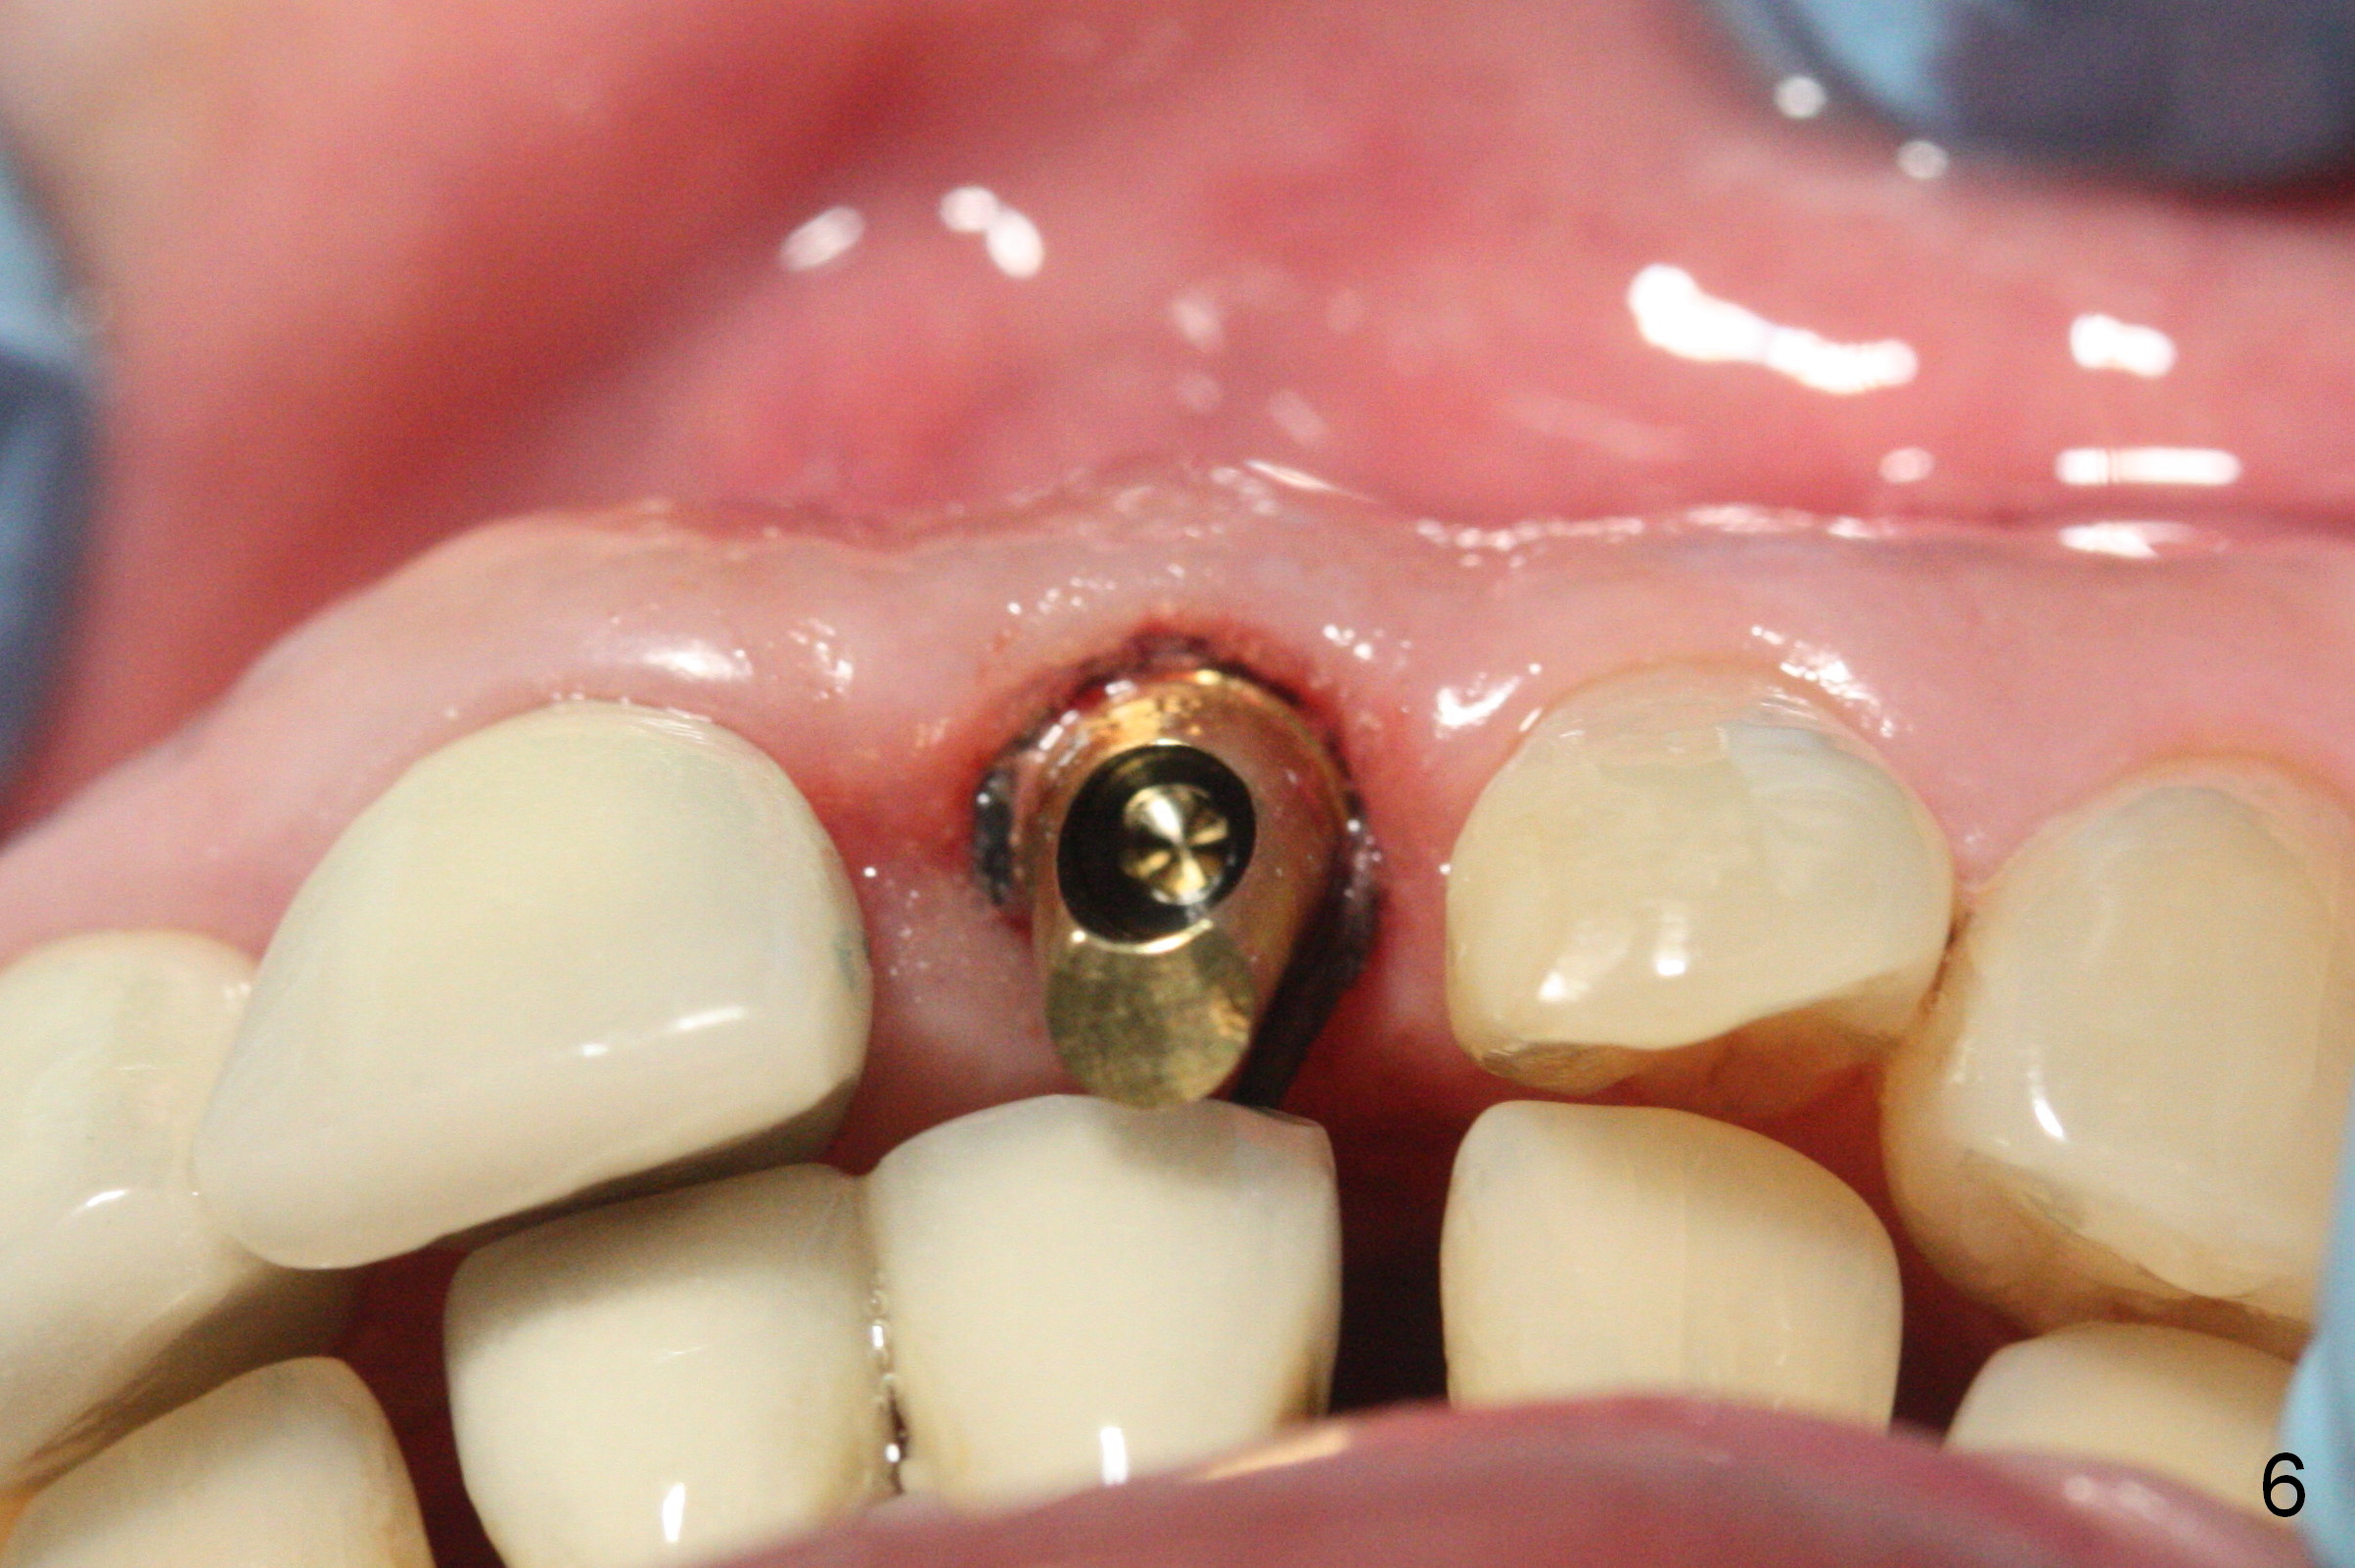

Gold-Coated Angled Abutment

When a permanent crown (Fig.1 C) is seated 5 months postop, it looks too long and bulky (as well as metal show through cervically), which is in turn due to buccal placement of the crown (Fig.2) and abutment (Fig.3).  By mistake, abutment is changed from 4.5x15°, 3 mm cuff to 4.5x15°, 2 mm cuff (Fig.4-6); the profile appears to improve.  After prep (buccoincisal (Fig.4 ^) and linguoincisal), impression is taken.  The gold coating in the buccocervical area is untouched so that there should be no or minimal metal show through.  Please make a new crown as cosmetic as possible (not too bulky, especially buccocervical).  If you feel that the result will be the same as before, return the case.  The angled abutment may be changed 25°.  In fact the new crown looks better.